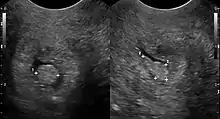

سليلة عنق الرحم يمكن رؤيتها أثناء فحص الحوض كإسقاطات لونها أحمر أو أرجواني من قناة عنق الرحم .يمكن التأكد للتشخيص عن طريق خزعة عنق الرحم، سوف تكشف عن طبيعة الخلايا الحالية .

سلائل عنق الرحم تشبه في نموها الاصبع في، أقل من 1 سم في القطر .وبصفة عامة فهي حمراء زاهية اللون، مع نسيج إسفنجي. من الممكن أن تتعلق علي عنق الرحم بواسطة ساق ( مسوقة ) وأحيانا تهبط في المهبل ،حيث يؤدي الي التشخيص الخاطئ بأنها سليلة بطانة الرحم أو السليلة تحت المخاطية .